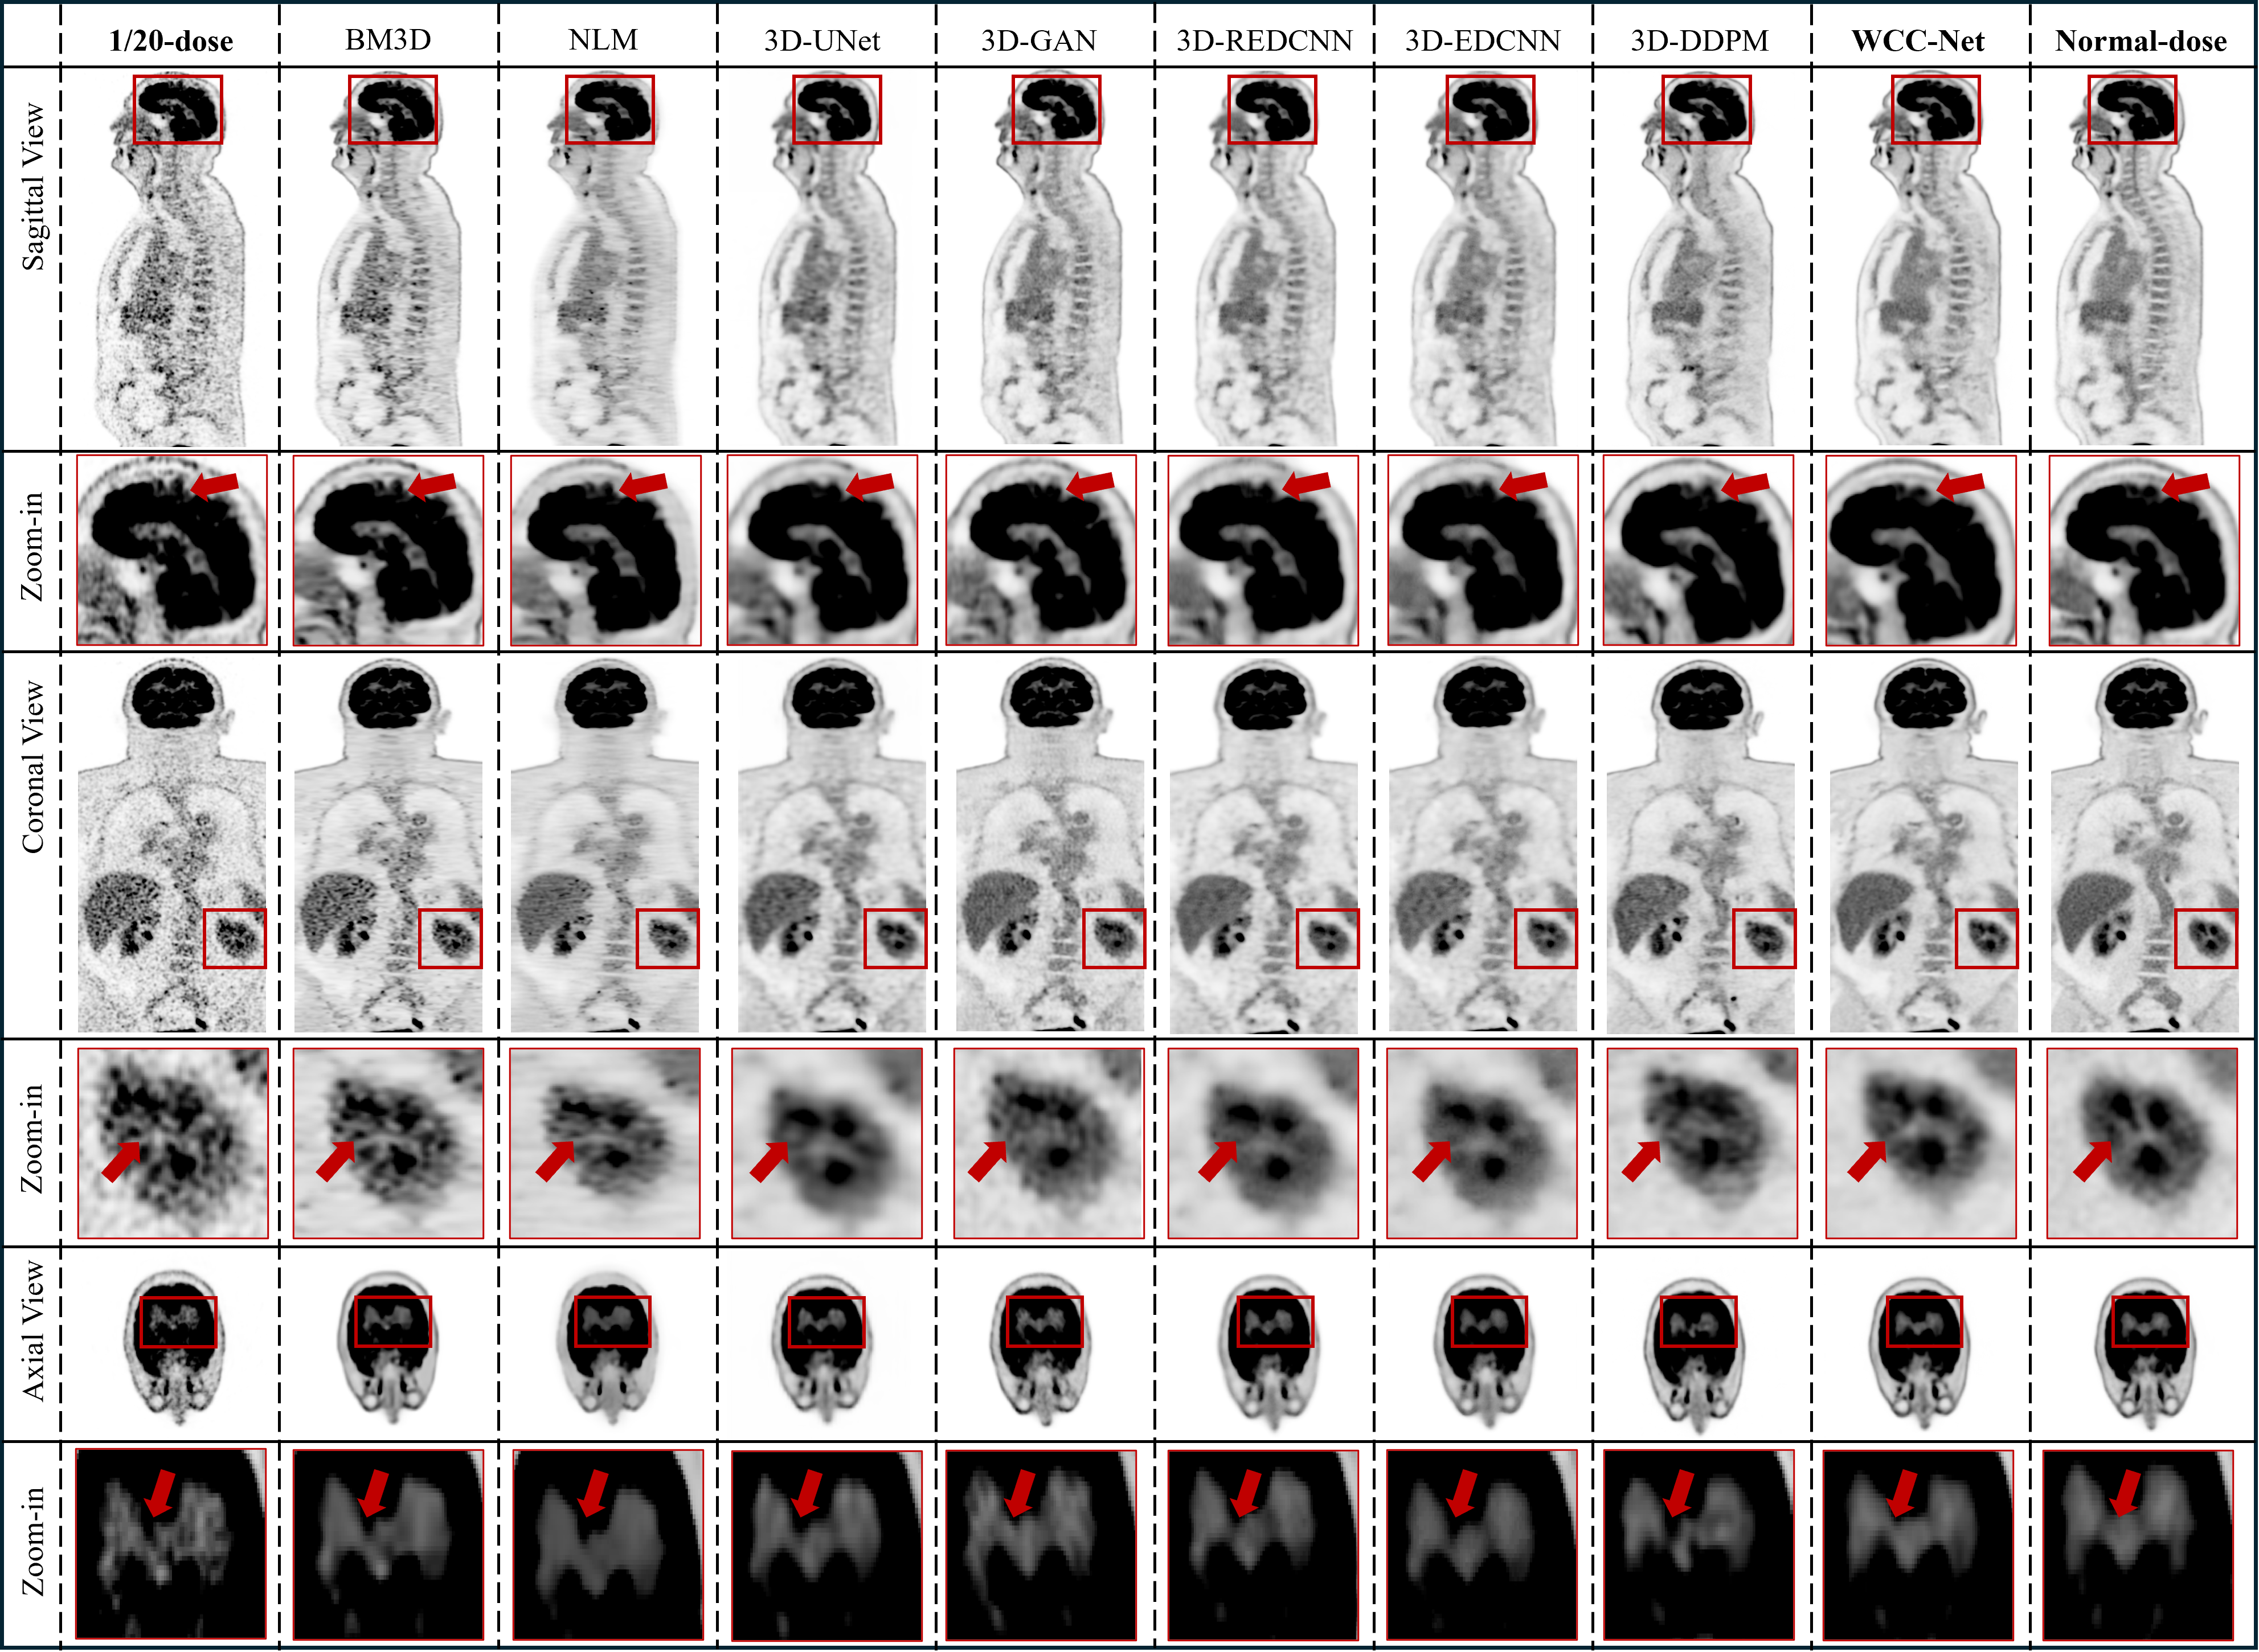

Figure 2: Qualitative comparison of whole-body PET denoising results. Sagittal, coronal, and axial views are shown for a representative test subject, comparing the 1/20-dose input, competing denoising methods, and the normal-dose reference. Zoom-in regions (red boxes) highlight areas of high uptake and fine anatomical structures.

Fig. 2 shows visual comparisons of whole-body PET denoising results in sagittal, coronal, and axial views. Classical methods such as BM3D and NLM reduce noise but suffer from oversmoothing, leading to blurred organ boundaries and attenuation of small high-uptake structures. CNN- and GAN-based methods (3D-UNet (Çiçek et al., 2016), 3D-REDCNN (Chen et al., 2017), 3D-EDCNN (Liang et al., 2020), and 3D-cGAN (Wang et al., 2018)) produce sharper images but often exhibit locally inconsistent textures or residual artifacts, particularly in regions with complex uptake patterns. Although the diffusion baseline yields globally coherent denoising, fine anatomical details, including thin cortical boundaries and small lesions, remain partially smoothed. In contrast, WCC-Net consistently preserves fine anatomical structures while effectively suppressing noise, producing images that more closely resemble the normal-dose reference, especially in magnified regions highlighting high-uptake organs and tissue interfaces.

To further assess reconstruction fidelity, Fig. 3 presents signed error maps. Competing methods exhibit spatially clustered over- and under-estimation, particularly near organ boundaries and regions of rapid intensity change, whereas WCC-Net shows lower error magnitude and reduced spatial bias. This advantage is further supported by the intensity profile analysis in Fig. 4, where WCC-Net more closely follows the normal-dose reference across all anatomical directions, preserving peak uptake values and sharp transitions. These results demonstrate that wavelet-conditioned structural priors effectively guide the diffusion process toward anatomically faithful PET denoising.